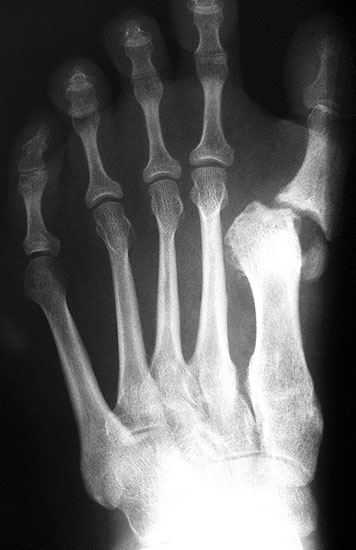

Die dorsoplantaren Röntgenaufnahmen zeigen eine Open-wedge Technik mit der normalerweise ein erhöhter intermetatarsaler Winkel gut zu korrigieren ist (Abbildung 3). Die Wirksamkeit einer Basisosteotomie ist umso größer, je proximaler diese durchgeführt wird. Je weiter distal die Osteotomie, umso geringer die Korrektur. Auf den postoperativen Bildern ist der distal unverändert große Abstand zwischen Metatarsale I und Metatarsale II erkennbar, bei gleichzeitiger Subluxation des Großzehengrundgelenks und dezentrierten Sesambeinen. Darüber hinaus finden sich initiale degenerative Veränderungen im Großzehengrundgelenk. Klinisch bestand eine hohe Weichteilspannung, bei verkürzter Extensor- und Flexor hallucis longus Sehne.  Daher wurde ein verkürzendes Verfahren zur Revision gewählt (Abbildung 4). Die Lapidusarthrodese stellt ein sehr zuverlässiges Verfahren zur Behandlung von Hallux valgus Rezidiven dar 9. Die Fusion des Tarsometatarsale-I-Gelenks kombiniert Stabilität mit einem hohen Korrekturpotenzial. Aufgrund der verfahrensimmanenten Verkürzung des ersten Strahls und der in diesem Fall bereits präoperativ vorhandenen Transfermetatarsalgie wurde die Entscheidung für eine verkürzte Weil-Osteotomie am zweiten bis fünften Strahl gefällt. Die Kombination beider Verfahren führte zu einem homogenen Metatarsale-Index und zu einer gleichmäßigen plantaren Druckverteilung 10. Die Hallux valgus interphalangeus Fehlstellung wurde mit einer Akin-Osteotomie korrigiert.